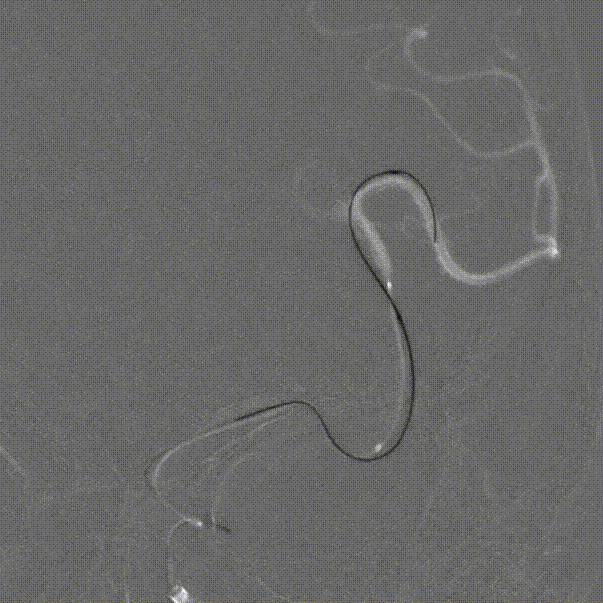

微导丝、微导管到位:

通路建立完成后,微导丝瘤内成袢,超选至大脑中动脉远端,支架微导管到位。

弹簧圈微导管到位。

Lattice远端释放:

Lattice输送到位后,透视下将支架远端定位于大脑中动脉M2段,回撤微导管原位释放支架,可见在支架头端机械球囊的辅助下,支架远端打开良好,头端导丝不位移。

继续释放支架至尾端,回撤微导管,支架自然打开贴壁满意,回撤球囊。

Vaso-CT显示支架打开及贴壁良好。